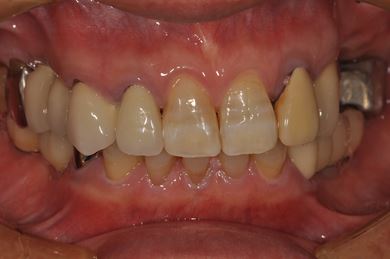

インプラントの症例写真 IMPLANT

骨再生インプラント治療

| 性別/年齢 | 男性 / 58歳 | ||||||||||||||||||||||||||||||||

| 主訴 | ブリッジがだめになったため、現在は部分入れ歯を使用しているが、インプラント治療を検討している。 | ||||||||||||||||||||||||||||||||

| 治療方針 | 左上奥の欠損部分をインプラント治療にて、機能的・審美的回復を行う。 | ||||||||||||||||||||||||||||||||

| 治療内容 | インプラント3本(GBR)、ハイブリッドセラミッククラウン3本 | ||||||||||||||||||||||||||||||||

| 総治療費 | 791,520円 | ||||||||||||||||||||||||||||||||

| 治療期間 | 10ヶ月 |